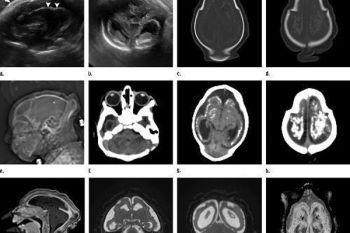

Jumlah penderita mikrosephalus dan cacat lahir tertentu lainnya 20 kali lebih tinggi pada kehamilan ...

Pusat Pengendalian dan Pencegahan Penyakit (CDC) Amerika Serikat, Rabu, mengatakan virus Zika menyebar dengan cepat di ...

Sebuah badan kesehatan Amerika Serikat menyatakan bahwa 279 ibu hamil di Amerika Serikat telah positif terjangkit ...